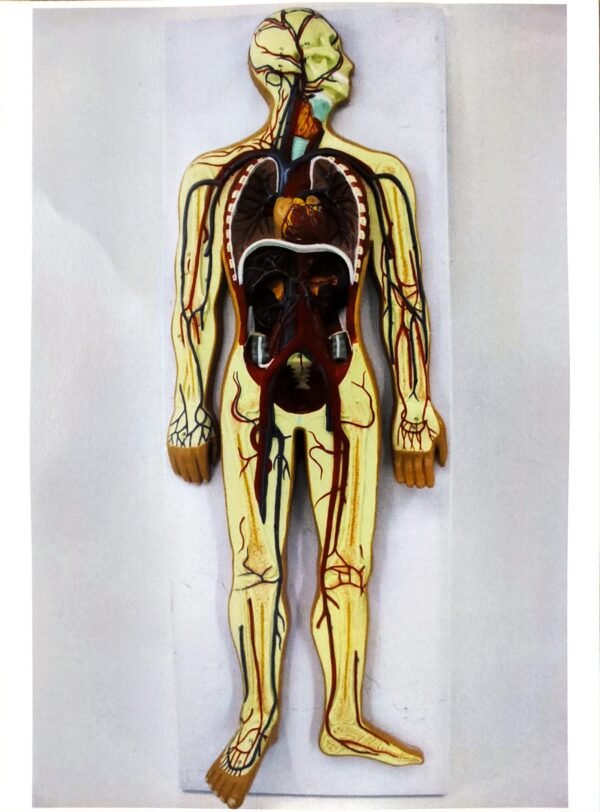

Blood Circulatory System model

* Size: 1/2 of natural size, height 86cm, width 30cm, thickness 5cm.